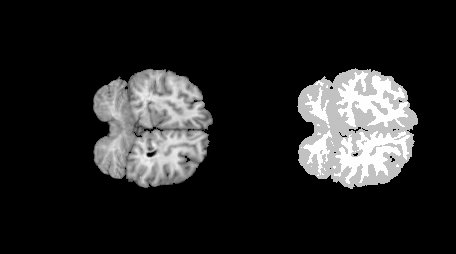

Irudi medikoetan tumoreak zehatzago mugatzen laguntzen du softwareak. Eta, horri esker, gaixotasunen egoera ezagutu dezakete. Ikerketa, zehazki, erresonantzia magnetikoaren bidez lortutako garuneko irudien azterketan oinarritzen da.

Irudien segmentazio prozesuari laguntzen dio programak: “Tumorearen irudia fondotik, atzealdetik, bereiztea da helburua. Ebakuntzaren unean tumorearen muga zehatz non dagoen jakiten lagun diezaioke medikuari —dio Bustincek—. Muga hori definitzea ez da batere erraza, eta horretarako pixel bakoitza aztertzen dugu”.

Erresonantzia bidez jasotako datuekin irudia osatzerakoan, aukeraketa egin behar du programak. Hau da, tumorearen parte diren pixelak zehaztu behar ditu. Matematikari esker, ezaugarri komun batzuk dituzten irudiko pixelak objektu beraren zatitzat jotzen ditu softwareak.